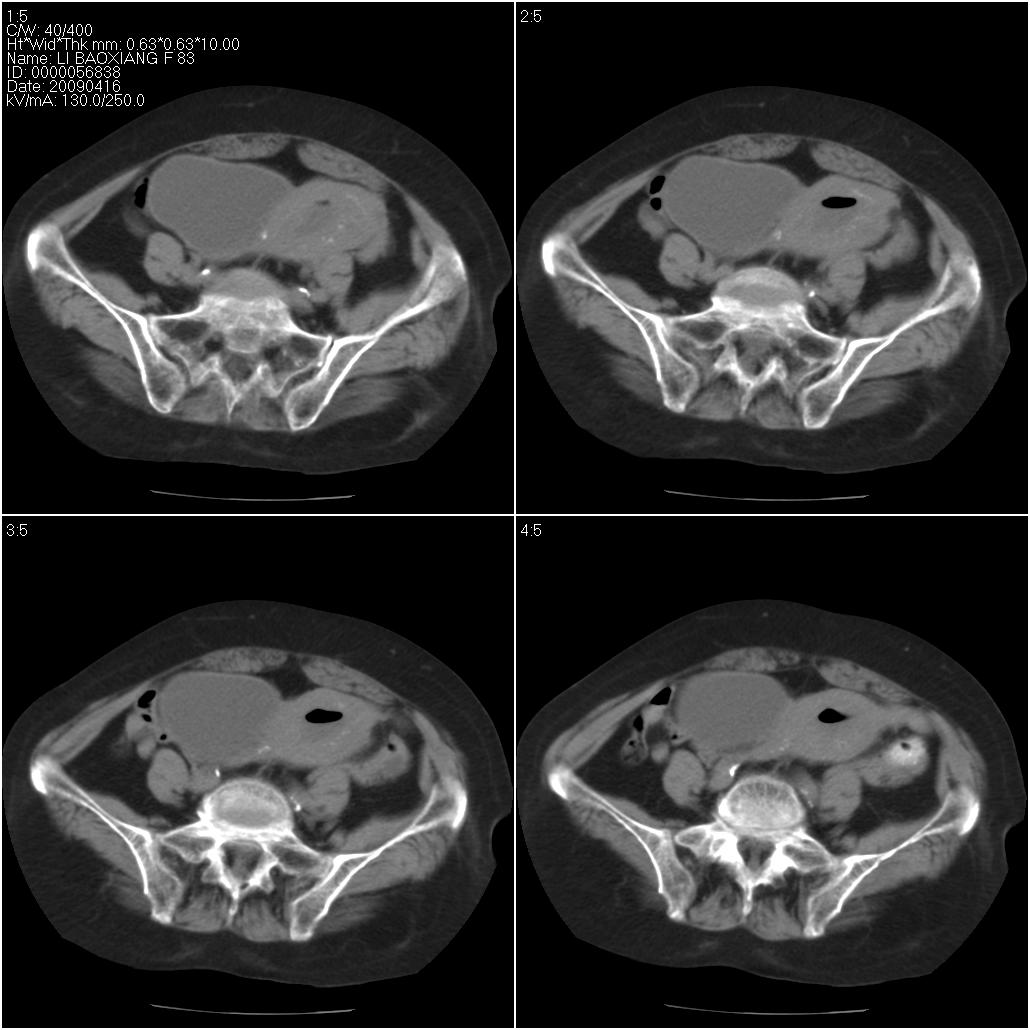

标题: CT19496:女性,83岁。阴道出血多年,患者一般情况良好。 [打印本页]

标题: CT19496:女性,83岁。阴道出血多年,患者一般情况良好。

乙状结肠病变累及子宫,建议结合妇科检查

考虑乙状结肠肿瘤累及子宫;建议行肠镜检查。

考虑:乙状结肠癌累及子宫,建议钡剂灌肠。

乙状结肠癌累及子宫

乙状结肠癌侵犯子宫可能性大。